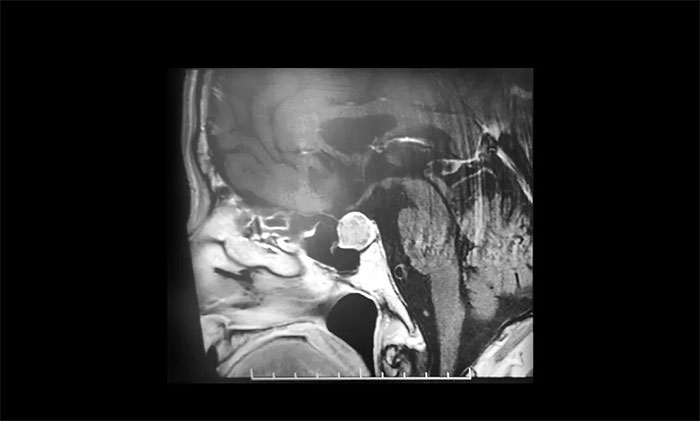

2021年初,王大爷在家人陪同下再到医院复查,鞍区MRI提示肿瘤较之前增大不少。医生表示肿瘤再继续长大可能会导致失明,手术已经迫在眉睫,但是手术风险也随之增大。为谨慎起见,家人商议决定到上海大医院求医,辗转打听后,王大爷慕名转入上海蓝十字脑科医院。

▲ 垂体大腺瘤超蝶鞍生长

入院后,鞍区MRI平扫+增强显示:蝶鞍扩大,鞍内肿块样灶,大小约1.6×1.4×1.2cm,鞍底轻度下陷。神经外科6B病区潘仁龙主任指出,垂体肿瘤超蝶鞍生长,压迫到视神经,使患者视物出现异常,一般1-3cm的大腺瘤或大于3cm的巨大腺瘤,都会引起不同程度的视力问题。

李士其教授、潘仁龙主任、吴治群博士会诊后指出:从影像学资料上看,发现瘤体较大,属于垂体大腺瘤,瘤体占据鞍区,视神经、视交叉受压,所以需要马上进行手术切除,解除压迫,如任其发展,很可能会有失明的风险。